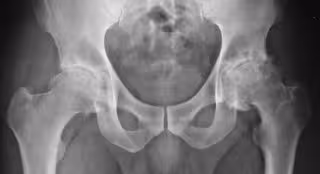

El líquido lubricante de las articulaciones desempeña un papel clave en el dolor de la artrosis

Artrosis

La artrosis causa dolor y rigidez en las articulaciones, y en algunas personas hinchazón y sensibilidad de las articulaciones. La afección afecta la calidad de vida de un individuo y su atención cuesta millones a la economía global, tanto directamente en términos de costos de atención médica como indirectamente debido al impacto en la vida laboral del individuo.

Esta patología reumática se ha considerado en gran medida como un trastorno degenerativo en el que el dolor se produce por el daño y el desgaste del hueso y el cartílago. Sin embargo, en los últimos años ha quedado claro que no se limita al daño del cartílago, sino que es una falla de toda la articulación, con la inflamación (la respuesta del cuerpo al estrés y las lesiones) que contribuye de manera importante al dolor experimentado por los pacientes.